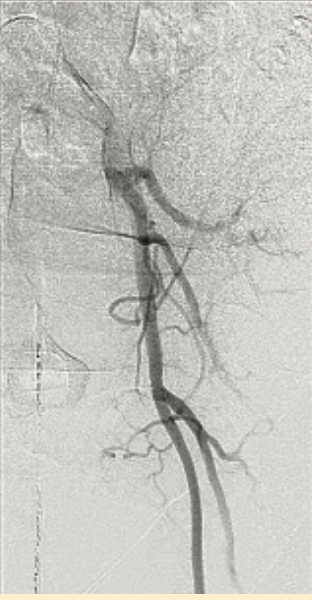

We planned to use cerebral protection during the case upfront, but the patient was known to have anomalous origin of her bilateral carotid arteries off of a single branch from the aortic arch, separate from the right brachiocephalic, and an anomalous insertion of the brachicephalic to the distal arch (Figure 2). We performed an aortic arch angiogram using a 15 cc contrast injection through a 5 French (Fr) pigtail with the ACIST CVi system (ACIST Medical) (Figure 3, Video 1) to guide the cerebral protection device from the anomalous brachiocephalic to protect the carotids. We proceeded with laceration of the left coronary cusp aortic valve leaflet. Aortic root angiography was performed using the same 5 Fr pigtail and a 10 cc contrast injection (Figure 4), then coronary angiography to identify the left coronary cusp (Figure 5). The optimal alignment of the left coronary cusp was determined by using a 6 Fr Amplatz left (AL) 1 guide catheter and a 6 cc injection with a lower pressure injection (Figure 6, Video 2). Finally, after the laceration was completed and the valve deployed (using small test injections from the ACIST contrast injector) (Figure 7, Video 3), we performed peripheral angiography with the 5 Fr pigtail advanced from the contralateral iliac artery to ensure adequate hemostasis of the large 14 Fr sheath access site (Figure 8, Video 4).